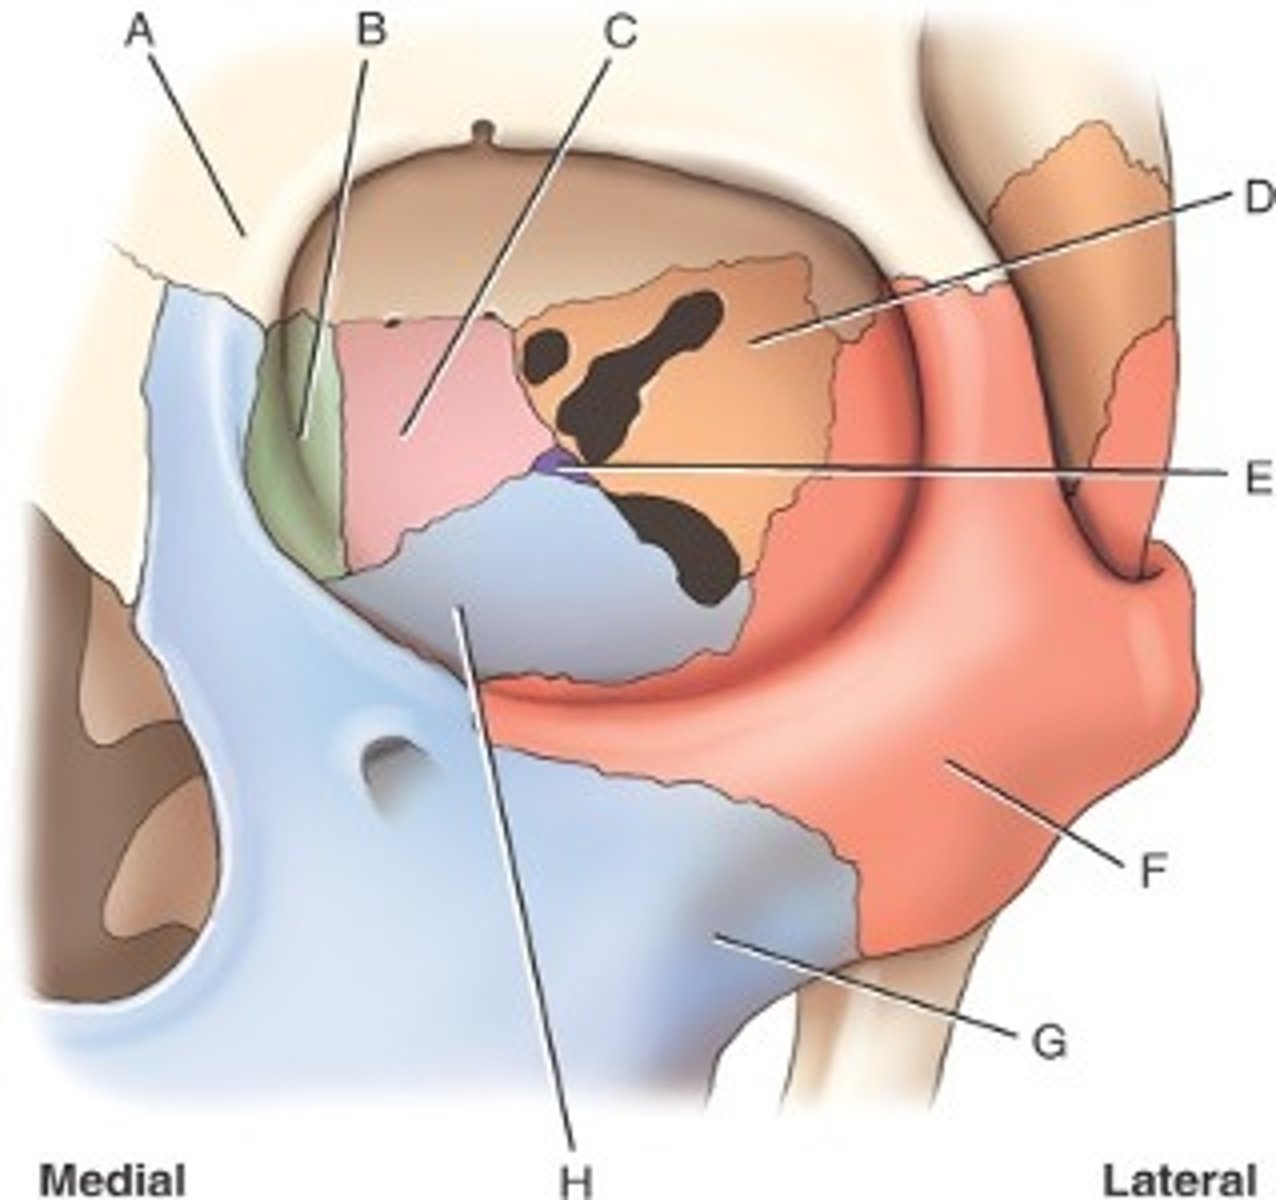

What is B

frontal bone

What is A

ethmoid

What is C

sphenoid

what is D

Palatine

What is E

Zygoma

What is F

Maxilla

What is G and H

optic foramen in orbit

sphenoid strut